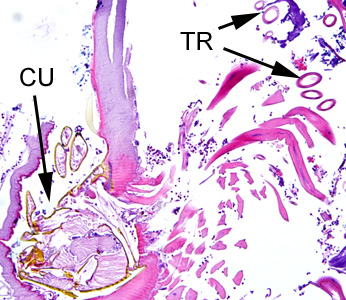

Case #275 – May, 2010

A 70-year-old female, who had recently returned from a trip to Madagascar, went to the hospital for a painful sensation on the underside of her left foot while walking. Examination of the area between the hallux and index toes revealed an ulcerative lesion. A biopsy was performed and sent to the Pathology Department for work-up. The specimen was sectioned, stained with hematoxylin and eosin (H&E) and examined by the attending pathologist. Figures A and B show what was observed at 40x magnification. Figures C and D show the same fields at 200x magnification, respectively. What is your diagnosis? Based on what criteria?

Figure C

Figure D